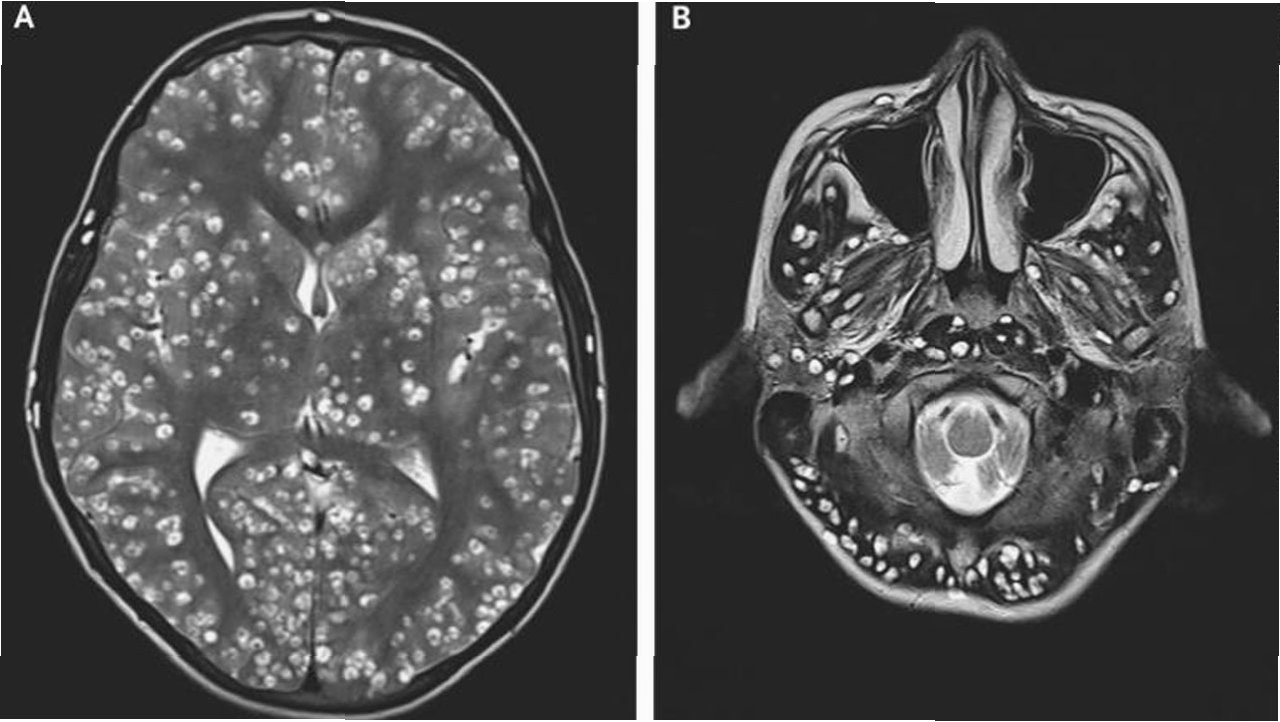

극심한 복통을 호소하며 병원으로 이송된 장씨는 검사 결과 기생충 감염으로 확진되었습니다. 의료진은 소화기관 손상과 함께 스파르가눔을 포함한 기생충이 체내에서 발견되었다고 밝혔습니다. 스파르가눔은 기생충 유충 단계를 의미하며, 이는 장씨가 겪은 고통의 원인이 되었습니다. 이 사건은 개인의 건강을 위해 과학적인 근거 없는 민간요법을 맹신하는 것이 얼마나 위험한지를 보여줍니다.